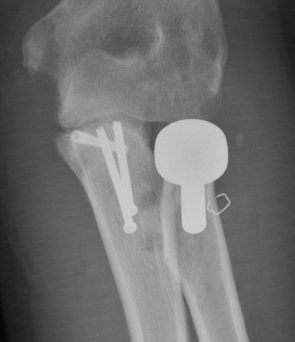

Universal posterior approach with radial head replacement and medial approach with medial buttress plate

coroncorocoronoid